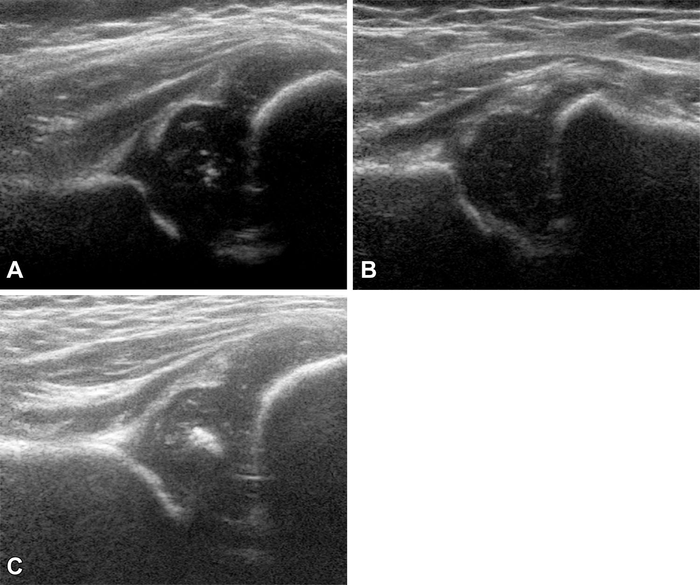

OAK BROOK, Ill. – A technique that uses ultrasound images to determine the depth and shape of the hip socket can accurately predict which infants with hip dysplasia will develop normal hip structure and which remain dysplastic, according to a study in Radiology . Researchers said statistical shape modeling improves on existing techniques and could spare many infants from unnecessary treatment.

Statistical shape modeling with ultrasound is an alternative method that quantifies the shape of the image of the hip with multiple reference points that each have an X and an Y coordinate in the 2D ultrasound image. It offers potential advantages over existing predictive models.

They developed statistical shape modeling on baseline ultrasound images and then correlated the model with persistent hip dysplasia on ultrasound after 12 weeks follow-up and residual hip dysplasia on pelvic X-rays around the age of one year.

The results showed that statistical shape modeling accurately predicted which hips developed to normal or remained dysplastic. It also identified hips that benefitted from treatment with the Pavlik harness, a soft splint that encourages normal development of the hip socket.